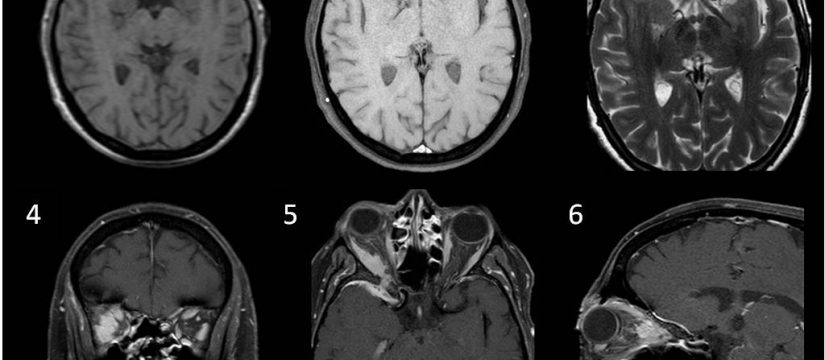

Historia Clínica

Varón de 40 años con esclerosis múltiple remitente-recurrente ya conocida, que consulta por disartria de varios días de evolución.